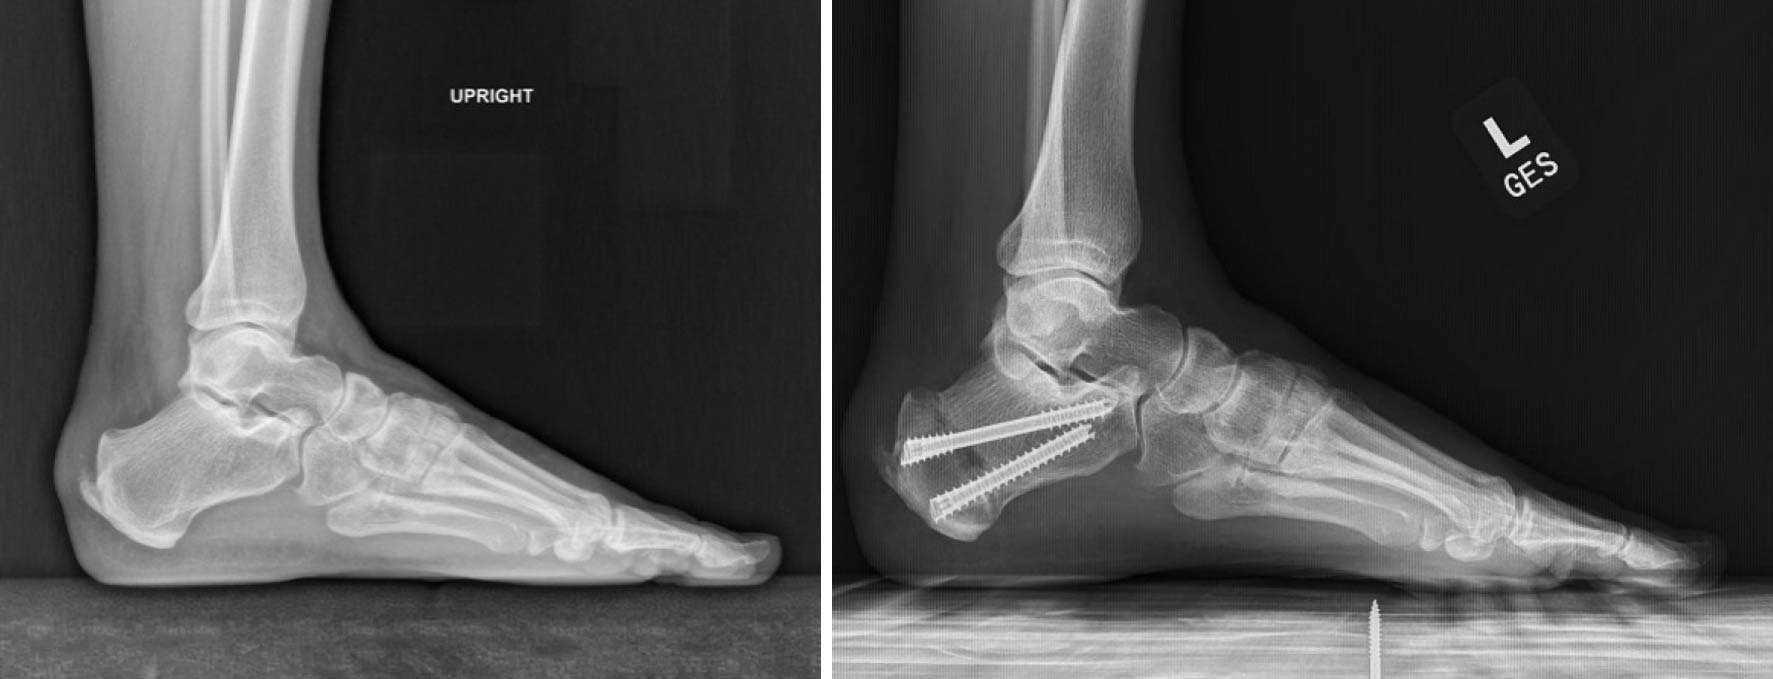

For millions of people, chronic heel pain is a relentless and frustrating battle. Conditions like insertional Achilles tendinopathy and Haglund’s deformity make every step a painful reminder of a problem that refuses to go away. For decades, the standard surgical solution has been an open procedure involving a large incision, cutting away the problematic bone spur, debridement and repair of the tendon and a long recovery.

But what if the conventional wisdom was wrong? What if the key to fixing the pain wasn’t removing the spur at all? A minimally invasive procedure, the MIS Zadek osteotomy is gaining traction among leading surgeons for its surprisingly effective and counter-intuitive approach. It challenges the very foundation of how we think about treating heel pain.

The core premise of the Zadek procedure is to change the biomechanical environment to allow the body to heal itself. By making a small cut in the heel bone and removing a wedge, the surgeon alters the angle by which the Achilles tendon inserts on the calcaneus. This decompresses the entire area, alleviating the tension and strain that caused the inflammation and pain in the first place, while allowing the tendon to heal naturally.